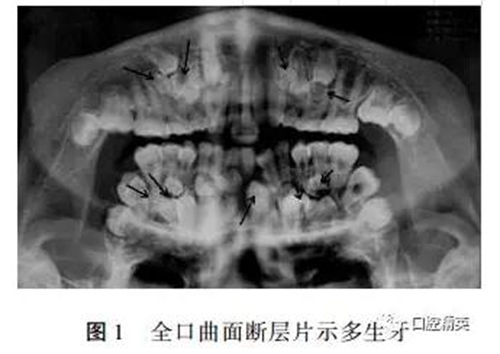

??茩z查:面部對(duì)稱,張口度未見(jiàn)異常,混合牙列:51、52、53、55、61、63、65、74、75、83、84、85未替換,14、16、22、24、26、31、32、33、36、41、42、46已萌出,咬合關(guān)系可。全口曲面斷層片示(見(jiàn)圖1):右側(cè)上頜前牙區(qū)及磨牙區(qū)可見(jiàn)5顆多生牙及未萌出的11、12、13、15,左側(cè)上頜前牙及前磨牙區(qū)可見(jiàn)3顆多生牙及未萌出的21、23、25,左側(cè)下頜前磨牙區(qū)可見(jiàn)2顆多生牙及未萌出的34、35,右下前磨牙及尖牙區(qū)可見(jiàn)4顆多生牙及未萌出的43、44、45。其中大多數(shù)多生牙牙冠形態(tài)近似前磨牙,部分牙齒牙根尚未形成,17、18、27、28、37、38、47、48牙胚形態(tài)基本正常。

關(guān)于多生牙好發(fā)部位:最常見(jiàn)于上頜中切牙之間,有報(bào)道對(duì)130顆多生牙進(jìn)行統(tǒng)計(jì),發(fā)生在11、21之間者占63.08%,也有報(bào)道上頜切牙區(qū)是多生牙多發(fā)部位,其次是前磨牙區(qū)。本例患者從發(fā)生部位看,上頜切牙區(qū)2顆,而前磨牙區(qū)11顆,右上磨牙區(qū)1顆,形態(tài)大多近似前磨牙,符合后者報(bào)道。關(guān)于多生牙數(shù):國(guó)內(nèi)報(bào)道85.4%的患者只有1~2顆多生牙,3顆以上者較少見(jiàn),多生牙多為單生,成對(duì)者少見(jiàn),而本例患者不但多生牙數(shù)目多,而且多發(fā)生在前磨牙區(qū),形態(tài)近似前磨牙,臨床上非常罕見(jiàn)。